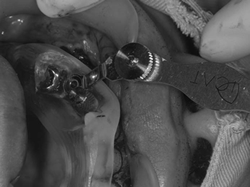

①ガイドを口腔内に合わせます。

②アイキャット専用の機材を用いて形成をします。サージカルガイドには事前に穴が空いてるので、形成時ずれることなく正確にドリリング(骨に穴をあけること)ができます。

③ドリリングが終わり穴が形成されました。

④インプラントが埋入されました。